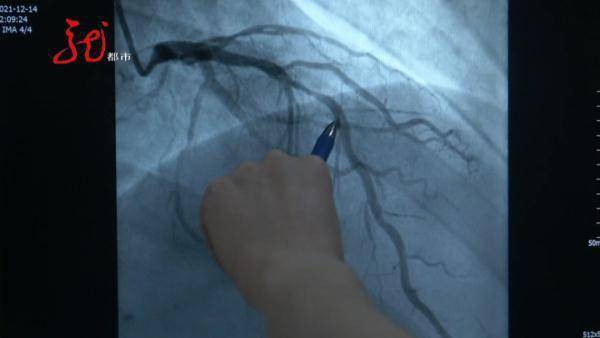

哈医大二院心内科 副主任医师 杨光

这是患者的右冠状动脉 , 正常的血管我们可以看到 , 从这儿开始 , 这样像一个C字型连接下来 , 而这个患者的血管 , 我们可以看到这个位置之后 , 中间黑颜色的血管消失了 , 完全“断开”了 , 这根血管完完全全地堵死了 。

右冠状动脉 , 是人体心脏的三根大血管之一 。 如果说 , 这是一位70岁老人的心脏 , 出现这种情况还算正常现象 , 而这恰恰是一位36岁男性的心脏 。